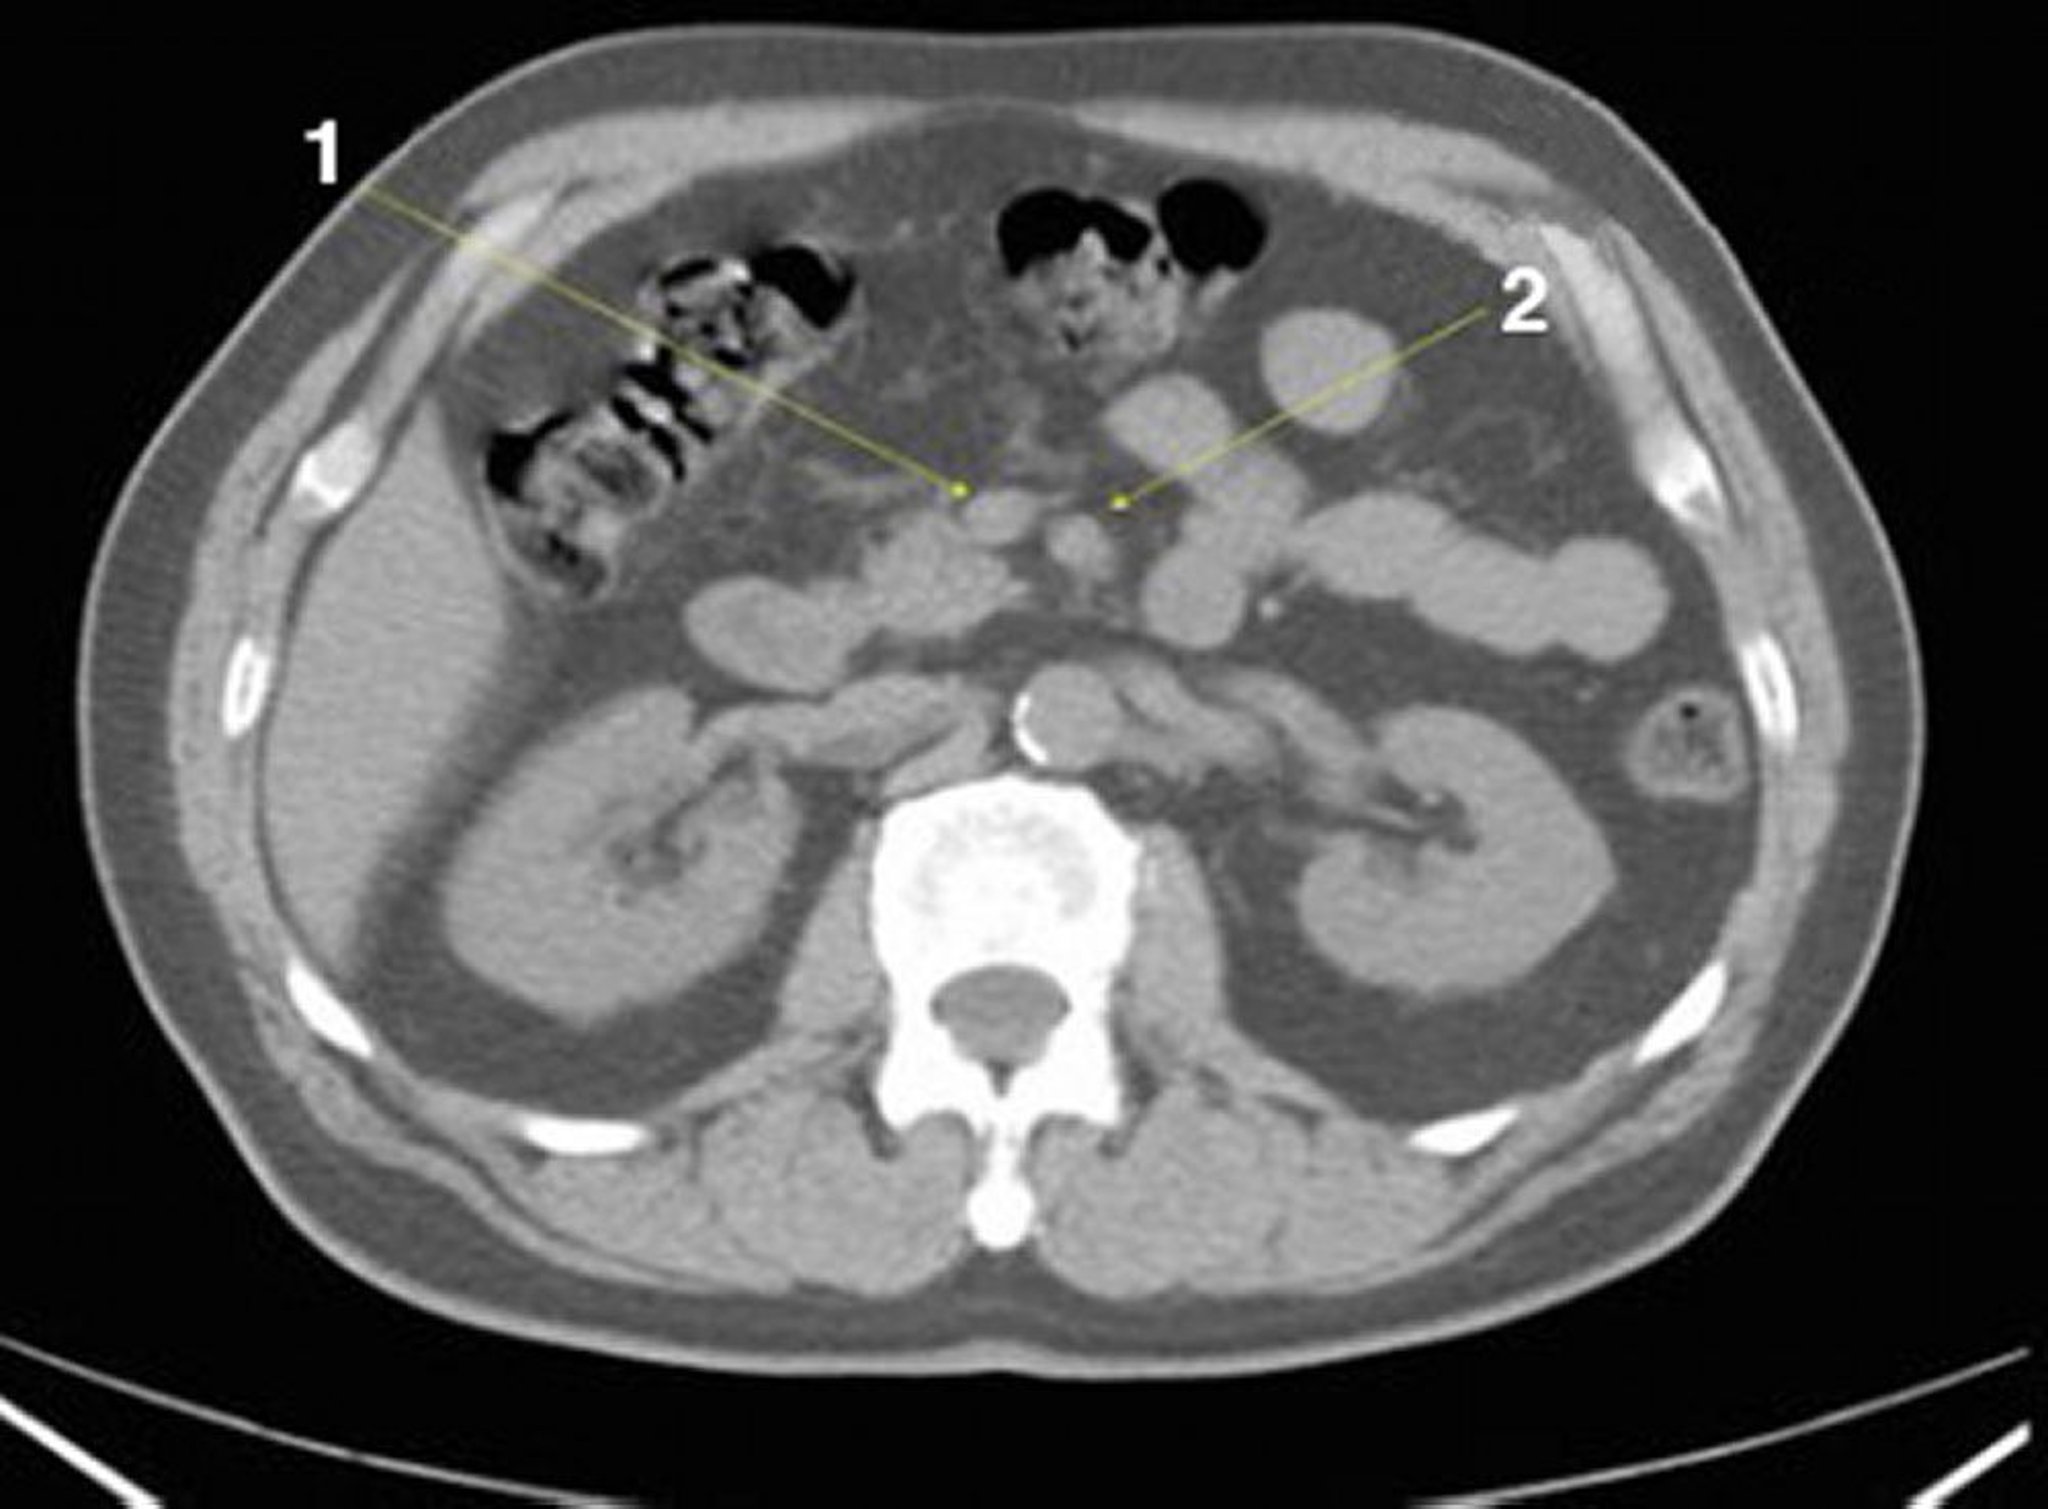

正常解剖を示した腹部および骨盤の単純CT画像(スライド13)

1 = 上腸間膜静脈;2 = 上腸間膜動脈。